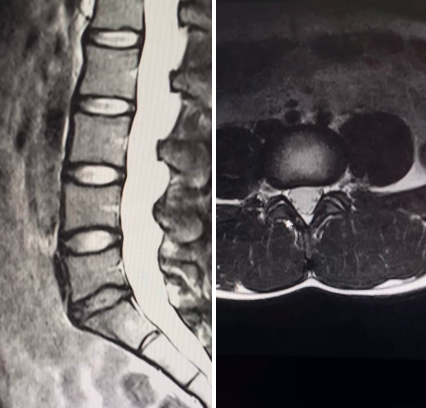

Интересный случай из практики МРТ:

- Женщина 55 лет, регулярные тренировки: мышцы плотные, поддерживают позвоночник, межпозвонковые диски — сохранены, даже пульпозные ядра (внутреннее желеобразное содержимое дисков) хорошо видны. Такое МРТ — почти как в молодости.

Этот пример наглядно показывает: движение продлевает ресурс позвоночника куда эффективнее, чем дата в паспорте. Начать можно с простого — прогулок, лёгкой зарядки, упражнений на укрепление мышц спины.